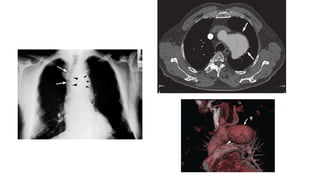

• Radiografía de tórax.

Es la primera prueba que se debe

realizar ante la sospecha clínica.

Típicamente se objetivará un

ensanchamiento mediastínico (60%)

• Angio-TC toracoabdominal: la técnica diagnóstica de elección para

diagnostico y planificar una eventual cirugía

Diagnóstico • Radiografía detórax. Es la primera prueba que se debe realizar ante la sospecha clínica. Típicamente se objetivará un ensanchamiento mediastínico (60%) • ECG: disección se extiende hacia las arterias coronarias puede aparecer elevación del ST.

• Angio-TC toracoabdominal:la técnica diagnóstica de elección para diagnostico y planificar una eventual cirugía - No se puede realizar en pacientes hemodinámicamente inestables con hipotensión grave y mala perfusión periférica